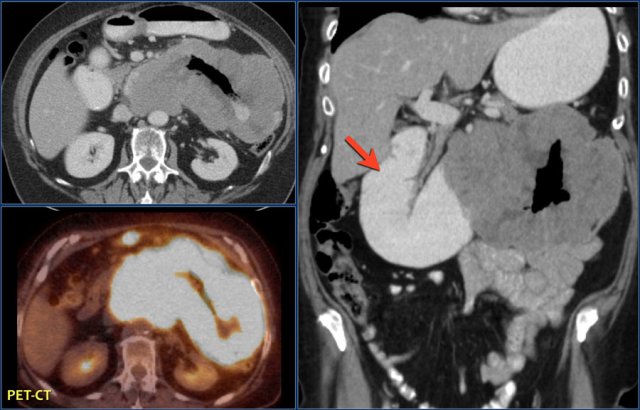

Here a typical lymphoma presenting as a large thick walled mass in the proximal jejunum with FDG uptake.

Dilated lumen at the site of the mass and prestenotic dilatation of the duodenum (red arrow)